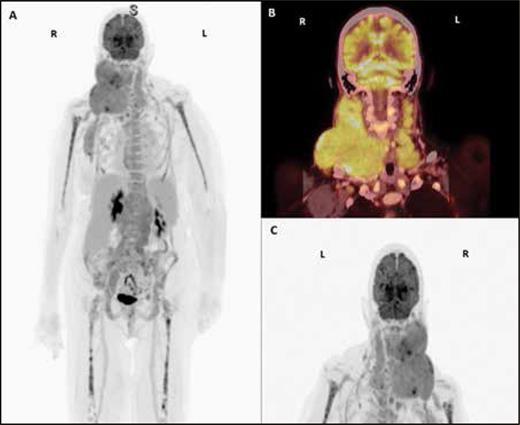

(A-C). PET/CT scan with contrast showing conglomerates of hypermetabolic lymph nodes in the right neck displacing the right oropharynx and extension to the right axilla, with an index lesion of 6.2 x 5.5 cm and standardized uptake value (SUV) of 8.2, and hypermetabolic lymph nodes in the left supraclavicular stations, with an index lesion of 1.7 x 1 cm and an SUV of 3.7.